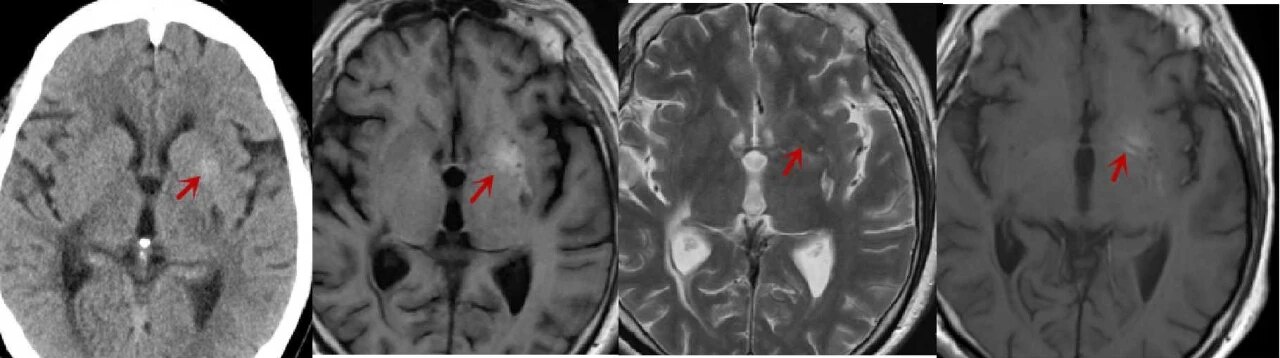

急诊头颅 CT 图像如下:

CT 示右侧尾状核头及豆状核弥漫性高密度,边界清晰,内囊密度无明显异常。

3 天后行 MRI 检查,图像如下:

T1WI 示病灶呈高信号,T2WI 呈低信号,DWI 信号不高,病灶边界清晰,无占位效应及周围水肿,内囊未累及。

case 1:

女,58 岁,右侧肢体持续性不自主扭动,既往糖尿病史 20 年,测血糖为 12.17 mmol/L,HbA1c 为 14.5%。CT 示左侧豆状核高密度,边界清晰。T1WI 示病灶呈高信号,T2WI 呈低信号,边界清晰,无占位效应及周围水肿,未累及内囊,增强后未见强化。